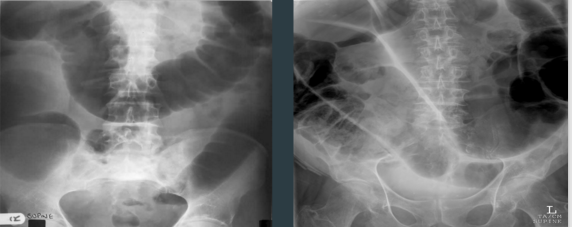

LARGE BOWEL OBSTRUCTION

TWO PATIENTS WITH

What are these two xrays showing?

Often occurs when?